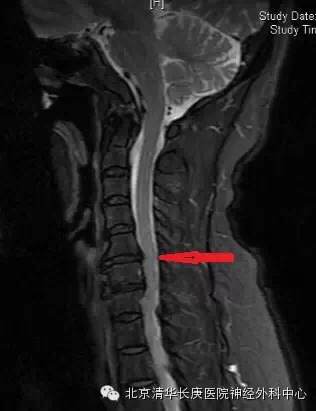

CT显示:C5-6,6-7椎间盘突出,后纵韧带骨化

术后MRI:C5-6突出椎间盘消失